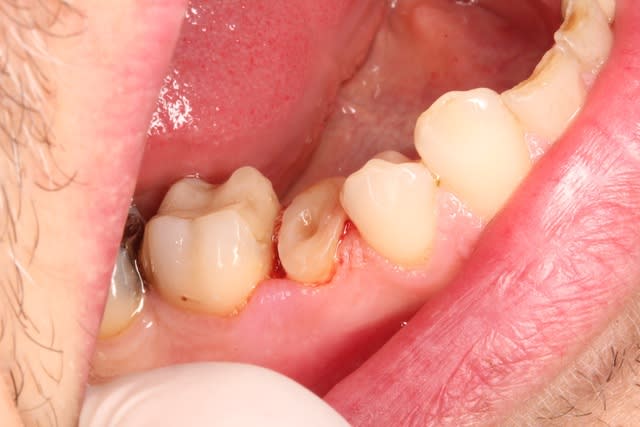

Voilà ce patient a consulté en Juillet pour une douleur à la mastication. Je regarde la radio, belle pêche sous les racines, en bouche, une fêlure traversant la dent dans le sens MD. A votre avis que faire dans ces cas et comment évaluez vous la réussite ou non de l'endo - CCC dans ces cas? Il n'avait aucune douleur quand j'appuyais transversalement de sur la moitié linguale ni sur la moitié vestibulaire (vers l'extérieur de la dent, pour "séparer" les dent).

J'ai émis de grosses réserves sur la pérennité du traitement et il a tout de même voulu procéder (j'avais même recommandé l'extraction, je ne travaille pas en France et quand le patient paie tout de sa poche c'est dur de "tenter", si ça merde y'a de grandes chances qu'il se retourne contre vous).

Bref je fais l'endo, et lisant de plus en plus de choses sur le sans-tenon (surtout le risque de fracture supérieur qu'il engendrait par perte de substance dentinaire) je me suis lancé dans un "Nayyar" core, compo descendant dans les entrées canalaires et par dessus une CCC.